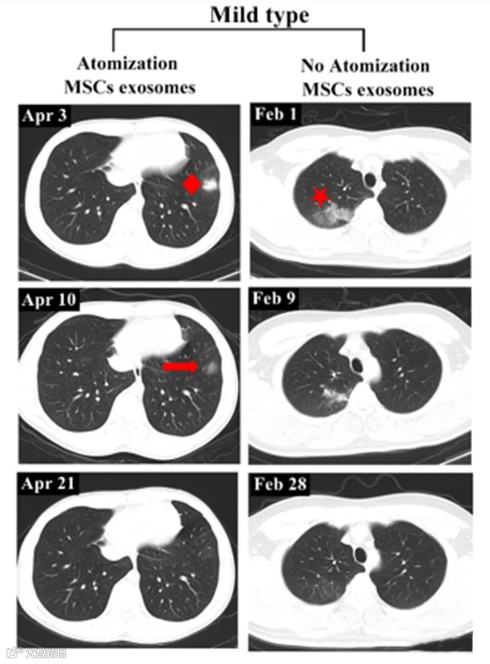

轻度患者前后影像变化:

2020年4月3日,该患者第一次CT扫描显示左肺下叶外有孤立结节,4月4日,患者接受外泌体雾化治疗,4月10日,第二次CT检查显示左肺下叶结节密度明显降低,大小也缩小,4月21日,第三次CT检查显示左下肺病灶完全吸收,从发现结节到完全吸收肺部病变所需的时间为18天。

相比之下,另一例患者(轻度病例,无雾化治疗)类似肺部病变的吸收时间为27天。

▲左:轻度病例,有雾化治疗

右:无外泌体雾化治疗的轻度病例